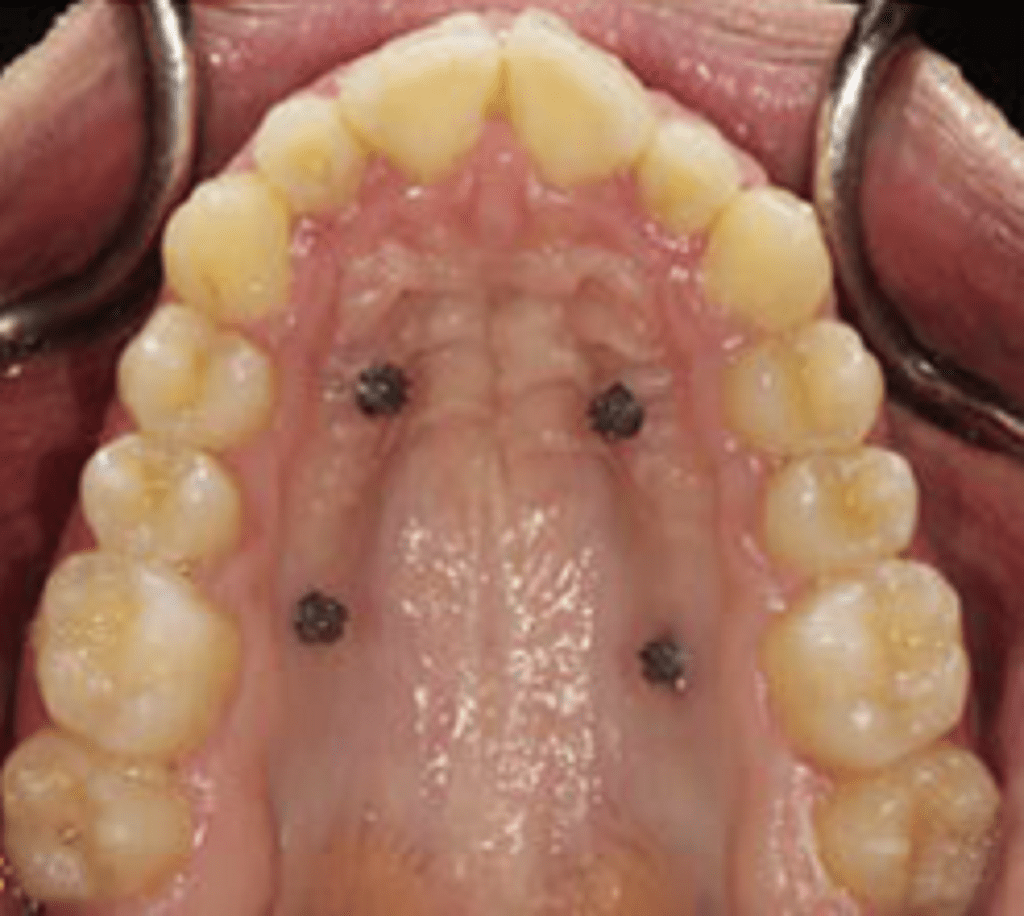

Temporary anchorage devices (TADs) can be used as skeletal anchorage in combination with the expansion appliance. Thus, miniscrews can be inserted on each side of the median palatal suture to replace teeth as anchorage units (Ludwig et al., 2013).

Also called MICROIMPLANT-assisted R.M.E technique (MARPE).

Miniscrews are employed onto the maxillary expanders that recruits palatal and nasal cortices. This provides anchorage that facilitates opening of mid-palatal suture and helps to overcome resistance from circum-maxillary sutures.

Paramedian area 3mm lateral to the suture in 1st premolar region is considered the most appropriate site for placement of miniscrews, anterior screws are placed in rugae.

Skeletal anchorage should permit orthopaedic change without adverse dental changes by applying force directly to the maxillary bone.